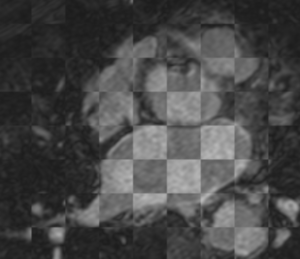

Example 1

Checker-filter: Pre and registered post LGE images Checker-filter: Pre and registered post LGE images Pre segmentation overlaid on registered post LGE Pre segmentation overlaid on registered post LGE

CARMA VecReg Check1.png

CARMA VecReg Check1-2.png